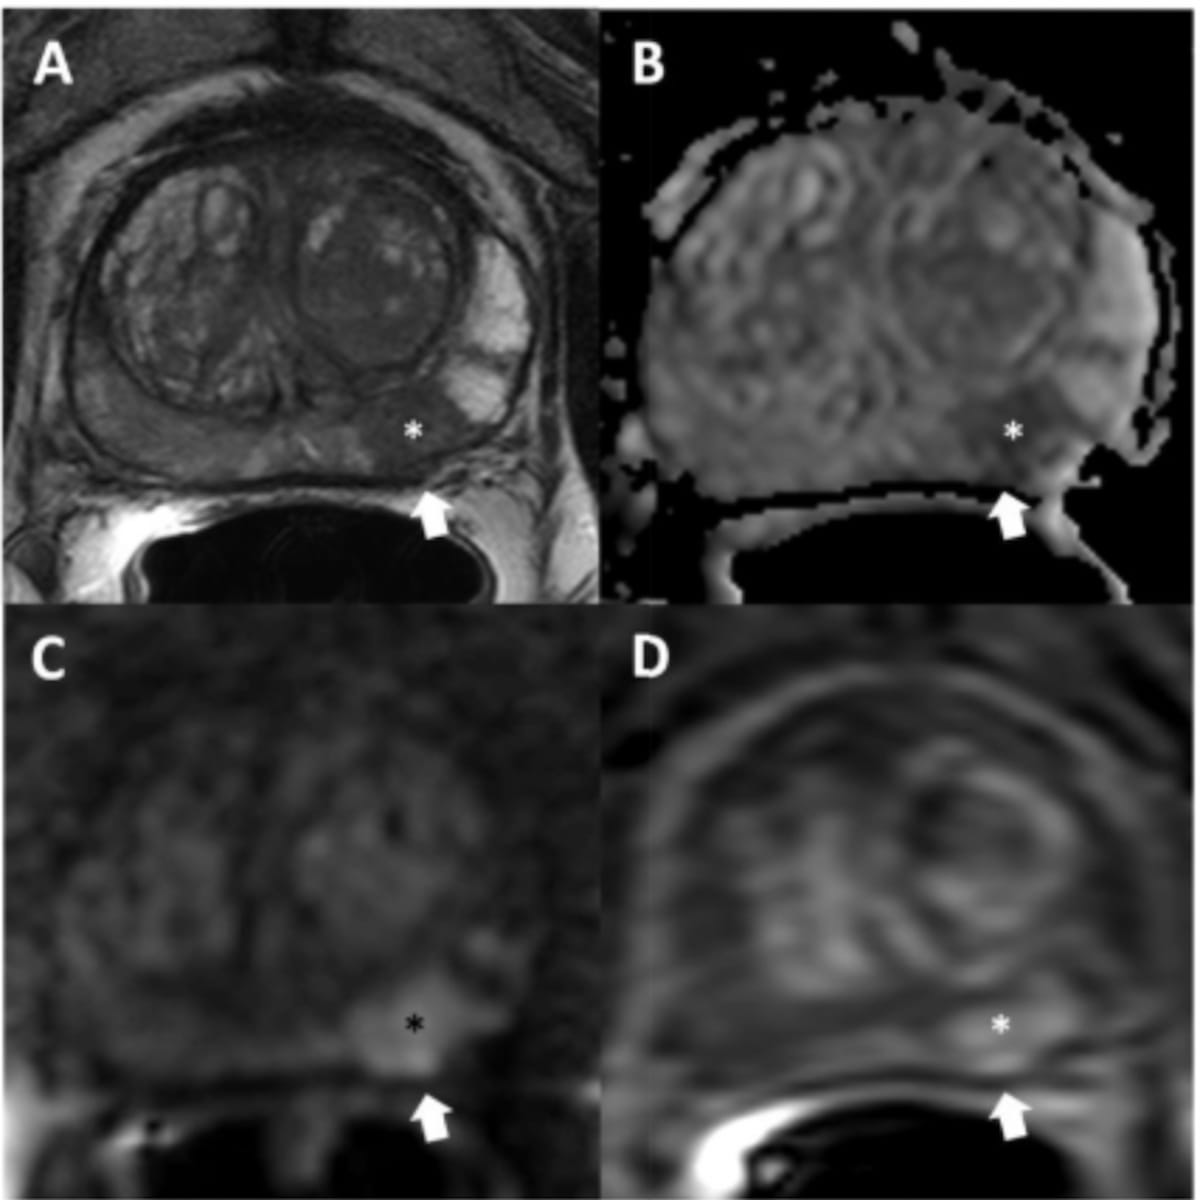

Utilizing a deep learning-based AI algorithm to differentiate between diagnostic and non-diagnostic quality of prostate MRI facilitated a 10 percent higher specificity rate for diagnosing extraprostatic extension on multiparametric MRI, according to research presented at the recent RSNA conference.